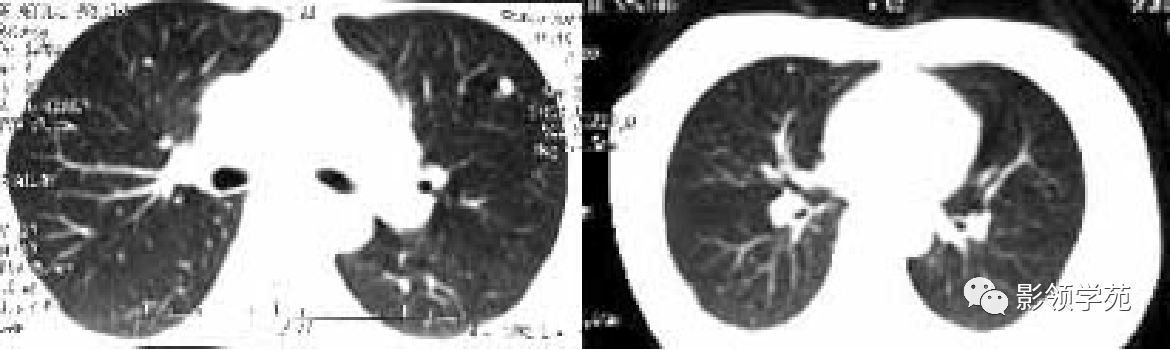

多发或单发结节,大小不一,边缘较清楚。少数结节伴出血时出现晕轮征,即有略高密度影像环绕结节,使病变边缘模糊。病变有钙化常见于骨肉瘤或软骨肉瘤转移。转移瘤亦可表现为空洞。两肺多发的小结节影具有随机分布的特点,HRCT显示结节位于小叶中心、小叶间隔、支气管血管束及胸膜,结节大小不均匀。

HRCT表现为沿淋巴管分布的结节。支气管血管束结节状增粗,并有结节,小叶间隔呈串珠状改变或增粗,小叶中心有结节灶,并有胸膜下结节。病变在两肺弥漫分布或局限于某一部位,以中下肺多见。常合并胸腔积液。约半数病人有纵隔及肺门淋巴结肿大。